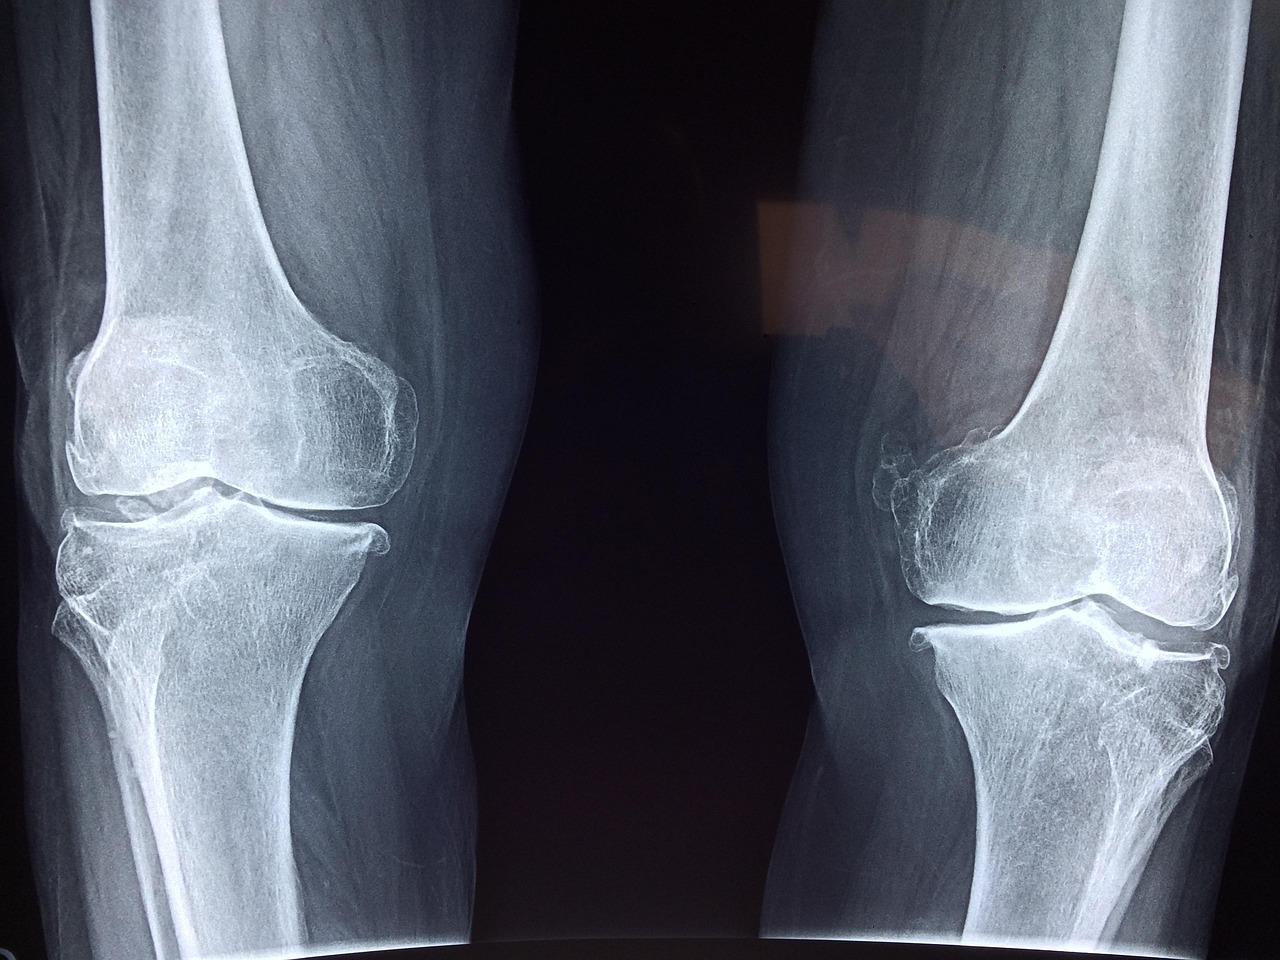

Higher bone density correlates with a reduced risk of osteoporosis and fractures. Research shows that HIIT promotes bone strength by stimulating bone formation through increased mechanical loading. The activity-level of HIIT effectively engages multiple muscle groups such as lower body, upper body, and core. This comprehensive engagement can lead to increased bone mineral density (BMD) across various sites including the hip, spine, and limbs. Enhanced BMD results from the dynamic exercises incorporated into HIIT routines, which force bones to continually adjust and adapt. Various studies highlight that older adults who participate in high-intensity resistance training, often seen in HIIT, significantly improve their bone health and reduce fracture risks. Exercises like jumping or sprinting stimulate responses from the osteocytes, which can enhance bone remodeling and health over time. Furthermore, individuals beginning HIIT at a younger age can expect lasting benefits, as higher bone density established during youth often translates into better bone health in later years. In conclusion, incorporating HIIT into one’s fitness regimen can prove essential in mitigating age-related bone loss and cardiovascular disease risks.